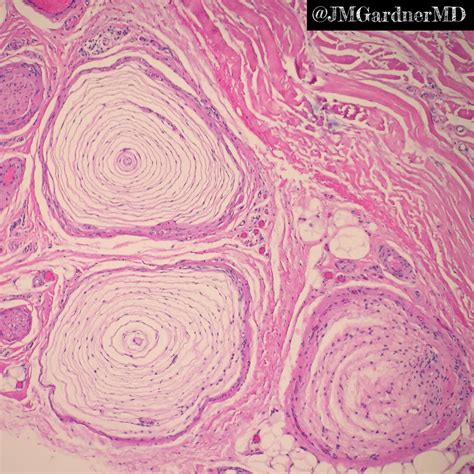

Structurally, these corpuscles resemble a sliced onion. This unique, multi-layered appearance is exactly where the term "lamellated" originates. The structure consists of a single unmyelinated nerve ending at the core, surrounded by layers of connective tissue cells called lamellae. This architectural design is not merely for show; it is critical for how the receptor transduces mechanical energy into electrical signals that the brain can process.

To fully grasp the function of the Pacinian lamellated corpuscle, one must look at its cellular architecture. Each corpuscle can reach up to 1 millimeter in length, making it one of the largest sensory receptors in the human body, large enough to be seen with the naked eye under the right conditions.

• The Central Core: This contains the unmyelinated nerve terminal, which acts as the transducer. When mechanical force is applied, this fiber depolarizes.

• The Lamellae: These are concentric layers of flattened epithelial cells separated by fluid. They act as a mechanical filter.

• The Capsule: The entire structure is encapsulated by connective tissue, which maintains the integrity of the corpuscle and ensures it responds only to specific types of stimuli.

The fluid between the lamellae is crucial. When vibration hits the skin, the fluid helps redistribute the energy, allowing the receptor to fire at the onset and release of pressure, but not during constant, steady pressure. This is why we become accustomed to the feel of clothing on our skin after a few minutes—our Pacinian corpuscles have stopped sending signals for steady, non-vibratory contact.